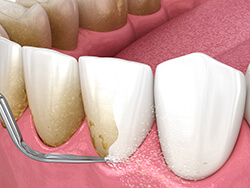

スケーリング

歯石除去

SRPとはスケーリング&ルートプレーニングの略で、 専用の器具を使用して、病原性の高い歯石を取り除く処置です。歯周病治療の1つで、ハンドスケーラーと呼ばれる専用の器具や、超音波の器具を用いて歯周ポケットの中(歯ぐきの中の歯の根に隠れている部分)の歯垢(プラーク)や歯石を取り除き、汚染された根面のセメント質や象牙質を除去してなめらかな根面にすることです。